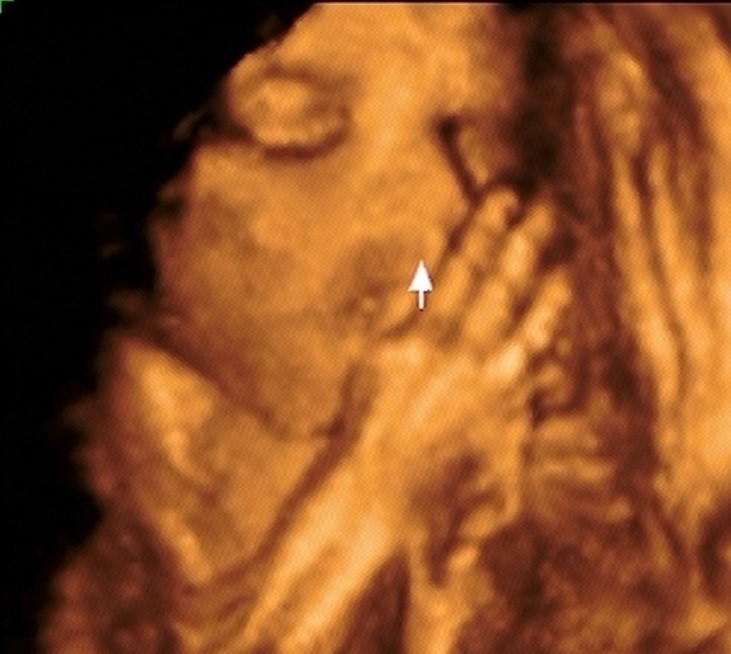

A teraz chciałam się pochwalić :)

Moja zdrowa, cudowna i upragniona Córeczka <3

• 4D (3).jpg

4D (3).jpg

83,9 KB · Wyświetleń: 105